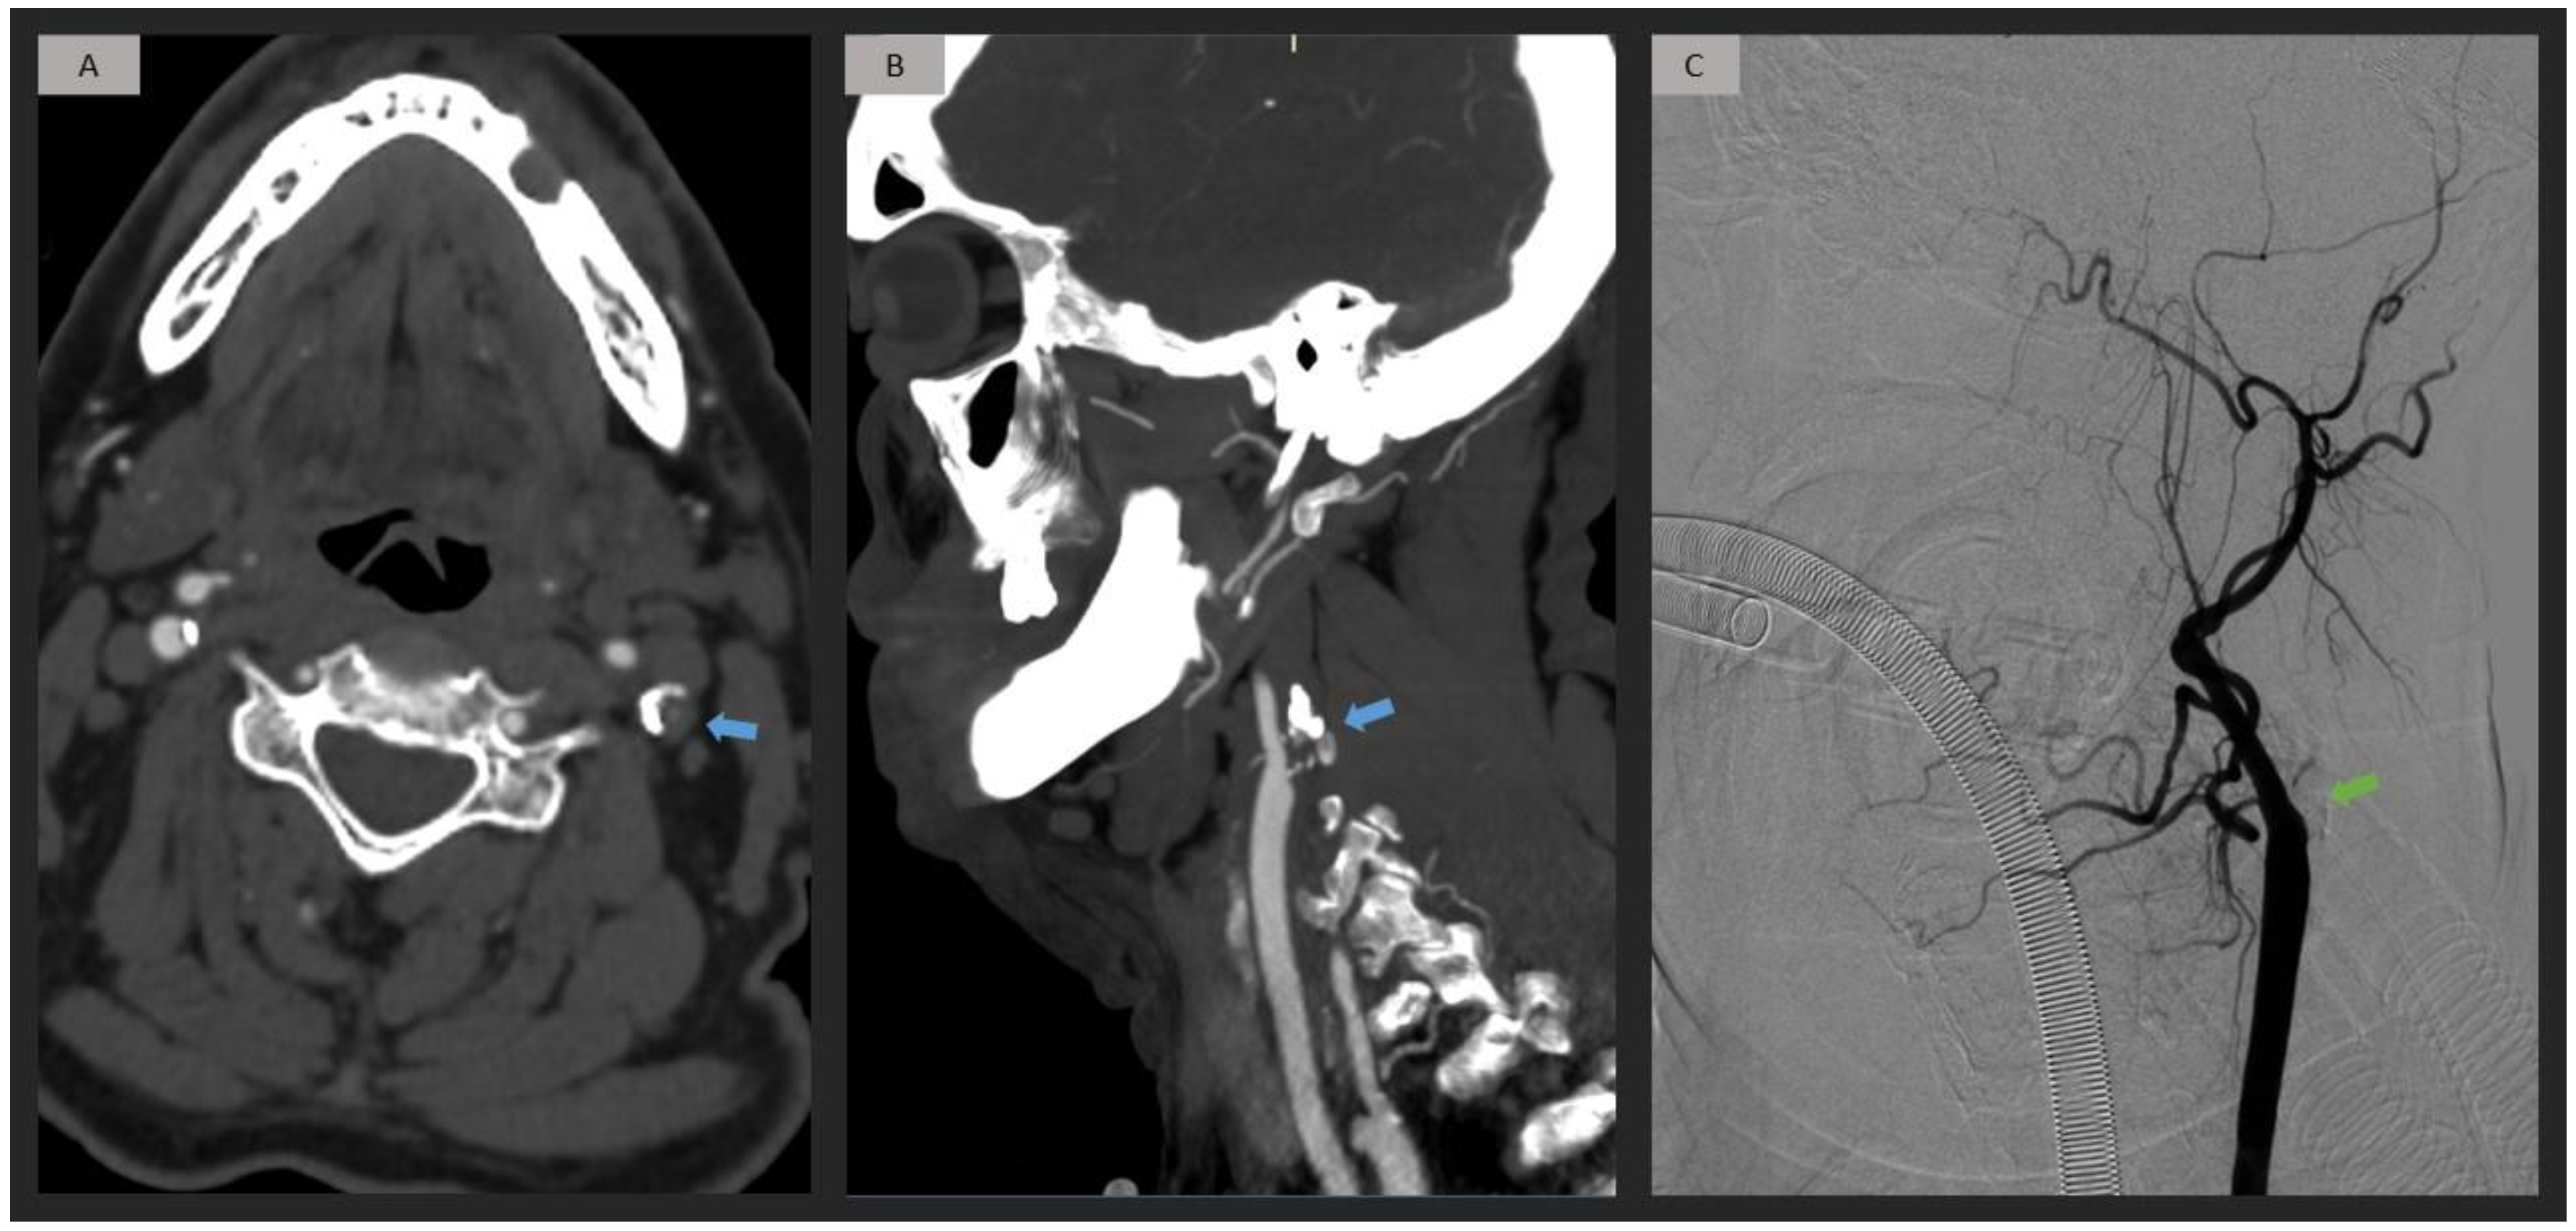

2.4. CTA Analysis

2.5. DSA Analysis

3. Results

4. Discussion